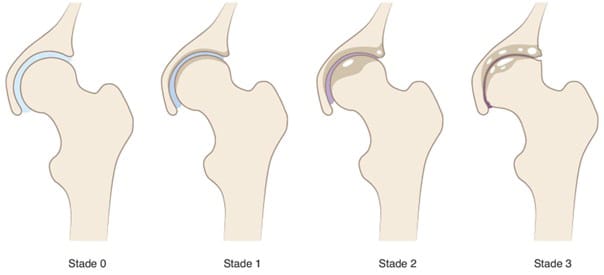

Tönnis classification of hip osteoarthritis (Figure 2):

- Grade 0: No sign of osteoarthritis.

- Grade 1: Early hip osteoarthritis: increased bone sclerosis, minimal joint space narrowing, absence or slight loss of femoral head sphericity.

- Grade 2: Moderate hip osteoarthritis: small bony cysts, moderate joint space narrowing, moderate loss of femoral head sphericity.

- Grade 3: Severe hip osteoarthritis: large bony cysts, severe narrowing or obliteration of the joint space, severe deformity of the femoral head.